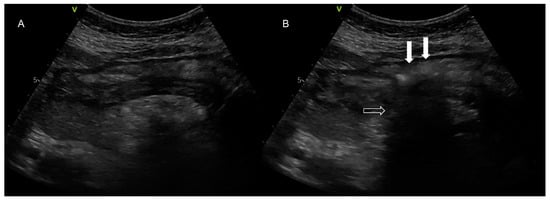

Two hundred and seventy-seven patients with COVID-19 ARDS were admitted in the ICU, and one was excluded from the analysis as he had undergone bariatric surgery 10 years previously (Figure 2, Table 1). All 282 patients, apart from three, had a NGT placed immediately after ICU admission. Those three patients were proned immediately after admission without a NGT, which was placed after they returned to the supine position. After the first six COVID-19 ARDS patients were admitted to the ICU, we faced one unfortunate NGT misplacement in a patient who turned to the supine position after he had been proned for sixteen hours. A chest X-ray was delayed, and enteral feeding was initiated after a “palpation” positive test. Eight hours later the patient became severely hypoxemic with increased secretions. Chest X-ray revealed that the NGT had been positioned in the right lower lung lobe (Figure 1). After that we decided to adopt a protocol of ultrasonographic confirmation of correct NGT position.

Figure 1. Chest X-ray in one of the first COVID-19 ARDS patients admitted in our ICU. The patient was turned from prone to the supine position on the 4th ICU day, late in the night, and nasogastric tube position was checked with palpation of a “flash” of air in the epigastrium, although there could not be observed any aspirated fluid. Enteral nutrition was started. Eight hours later the patient became hypoxemic, and increased tracheobronchial secretions were noted. A chest X-ray was ordered which revealed the NGT mispositioning in the right lower lobe. White arrows indicate the misplaced nasogastric tube in the Right Lower Lobe.